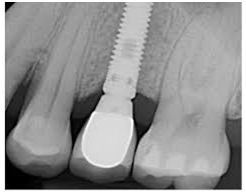

Dental Implants